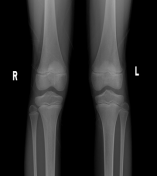

骨骺线是骨骺与干骺端之间的软骨,又称为“骺板”或“生长板”,在儿童腕掌指骨及膝关节的X光片上表现为一条较宽的透光带,它的闭合程度直接关系到孩子还有多少长高空间。

1.骨骺线未闭合:软骨还能继续骨化,孩子仍有很大长高潜力,这是正常生长的“黄金期”。

2.骨骺线部分闭合:软骨逐渐减少,生长速度放缓,剩余长高空间有限(通常每年增长不超过2-3cm)。

3.骨骺线完全闭合:骨骼停止生长,身高基本定型(仅脊柱可能有1-2cm弹性增长)。